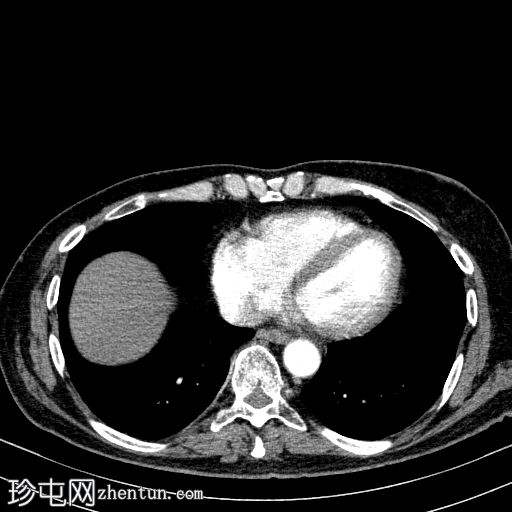

4.jpg

轴向C+动脉期

胰体尾弥漫性增大,特征为胰腺实质低强化,无明显坏死区域。

该病灶与以下表现相关:

胰周筋膜平面边界不清的污迹,无明显壁形成、气室、固体碎片或血液产物。

在疾病早期,可能出现胰腺肿大、胰腺组织低增强、胰周脂肪条带、积液和筋膜增厚。

在严重病例中,可能出现坏死或血管并发症。密切的临床监测和实验室检查至关重要。